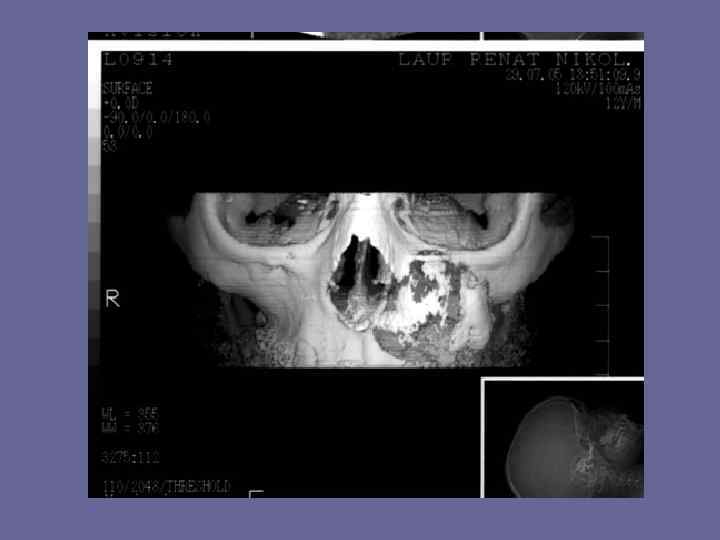

Компьютерная томография